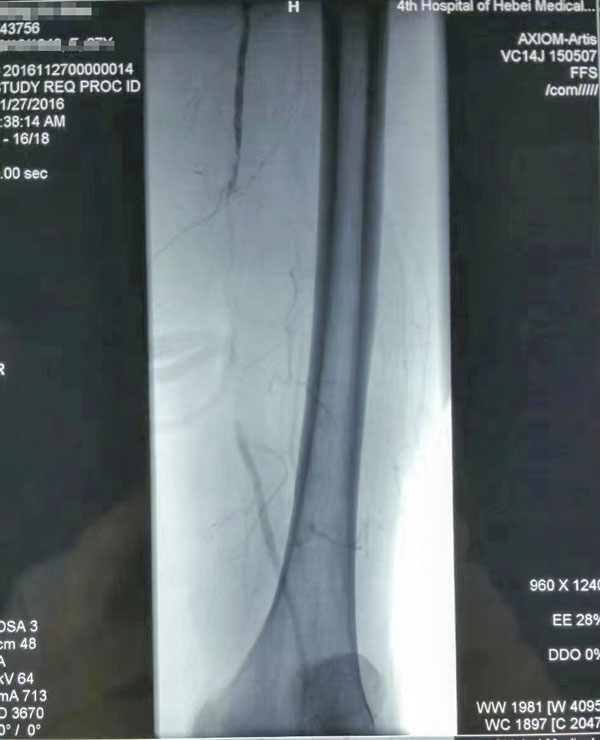

介入治療前后對比

糖尿病足重在預防,而預防和治療下肢血管病變是防治糖尿病足的有效措施。下肢血運重建是糖尿病下肢血管病變治療的根本采用球囊擴張開通狹窄或閉塞的下肢動脈(介入治療),恢復直達足部的血流,是治療糖尿病下肢血管病變的根本措施,具有立竿見影的效果這也是近年來在糖尿病足診治方面取得的又一新進展,為廣大糖尿病下肢血管病變患者解除了痛苦使糖尿病足患者截肢率由34%降至4%。世界防治糖尿病日到來之際,希望廣大糖尿病患者關注糖尿病下肢血管病變,保護自己的雙足,做到早發現、早治療,提升幸福感快樂每一天。